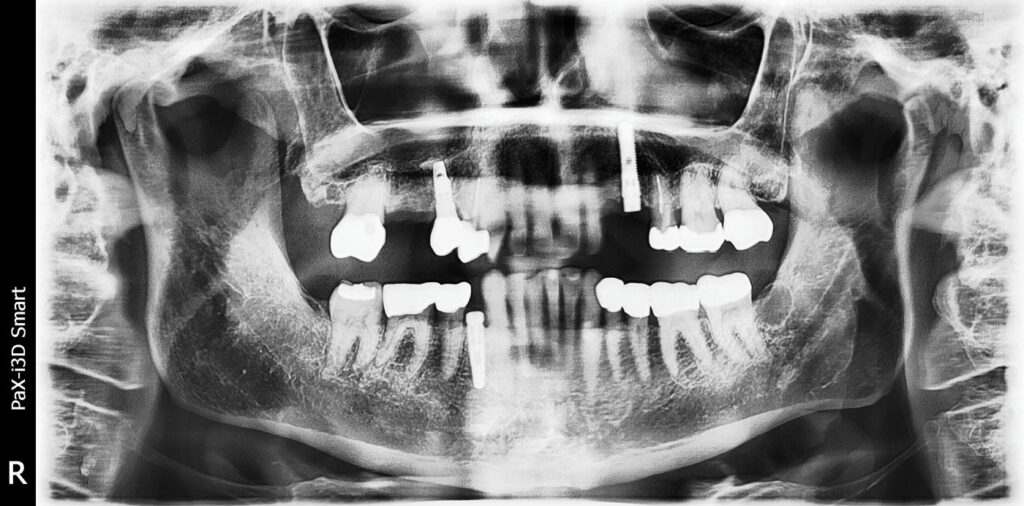

67-year-old woman with radiographic finding

A 67-year-old woman with an unusual finding on a panoramic film.